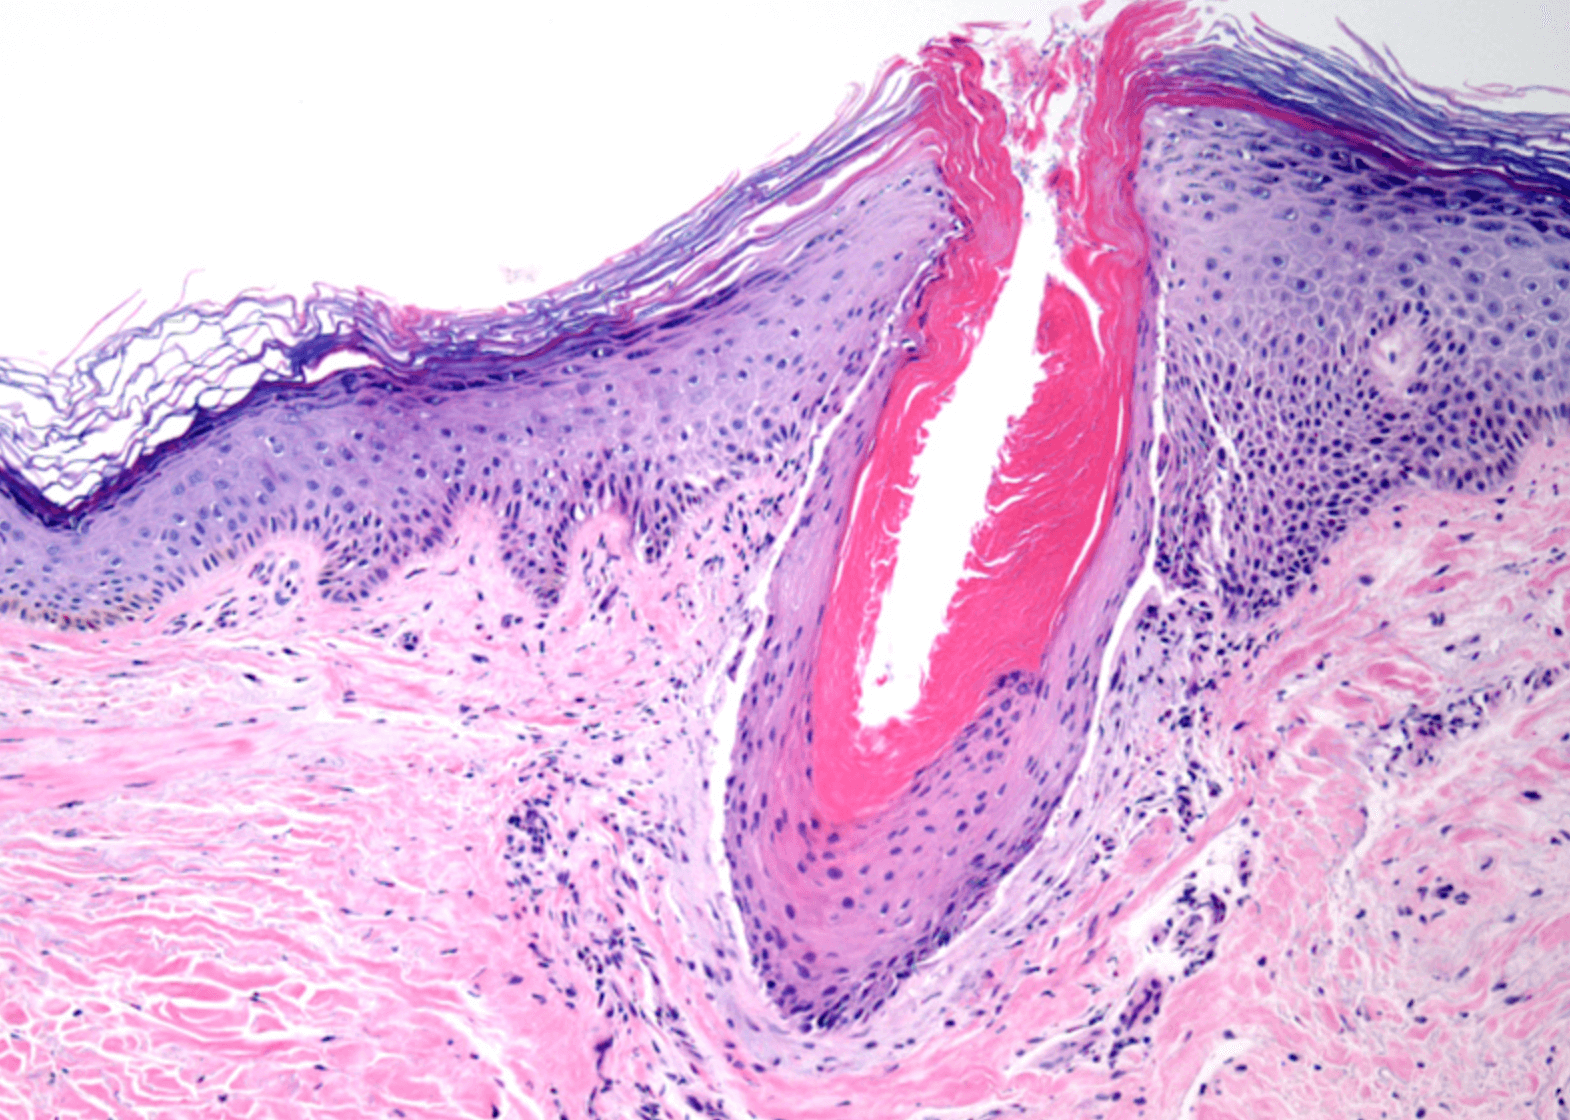

모공각화증

닭살돋은 느낌의 붉은 피부를 모공각화증 이라고 생각하시면 이해도가 쉬울것 같습니다. 이러한 작은 융기는 모낭을 막아 죽은 세포 이며, 보통 붉읂색 또는 갈색으로 나타납니다.

모공각화증은 팔뚝, 허벅지, 뺨또는 엉덩이에서 일반적으로 발생하고, 전염성 및 가려움증 같은 불편함은 유발하지 않지만 외관상 보기가 좋지 않습니다. 자세히 보면 징그럽다고 이야기 하는 사람들도 있으니간요.

모공각화증은 유해 물질과 감염으로부터 피부를 보호하는 단단한 단백질인 케라틴이 축척되어 발생하며, 케라틴은 모낭의 열림을 막아 거칠고 오돌토돌한 피부를 만듭니다.